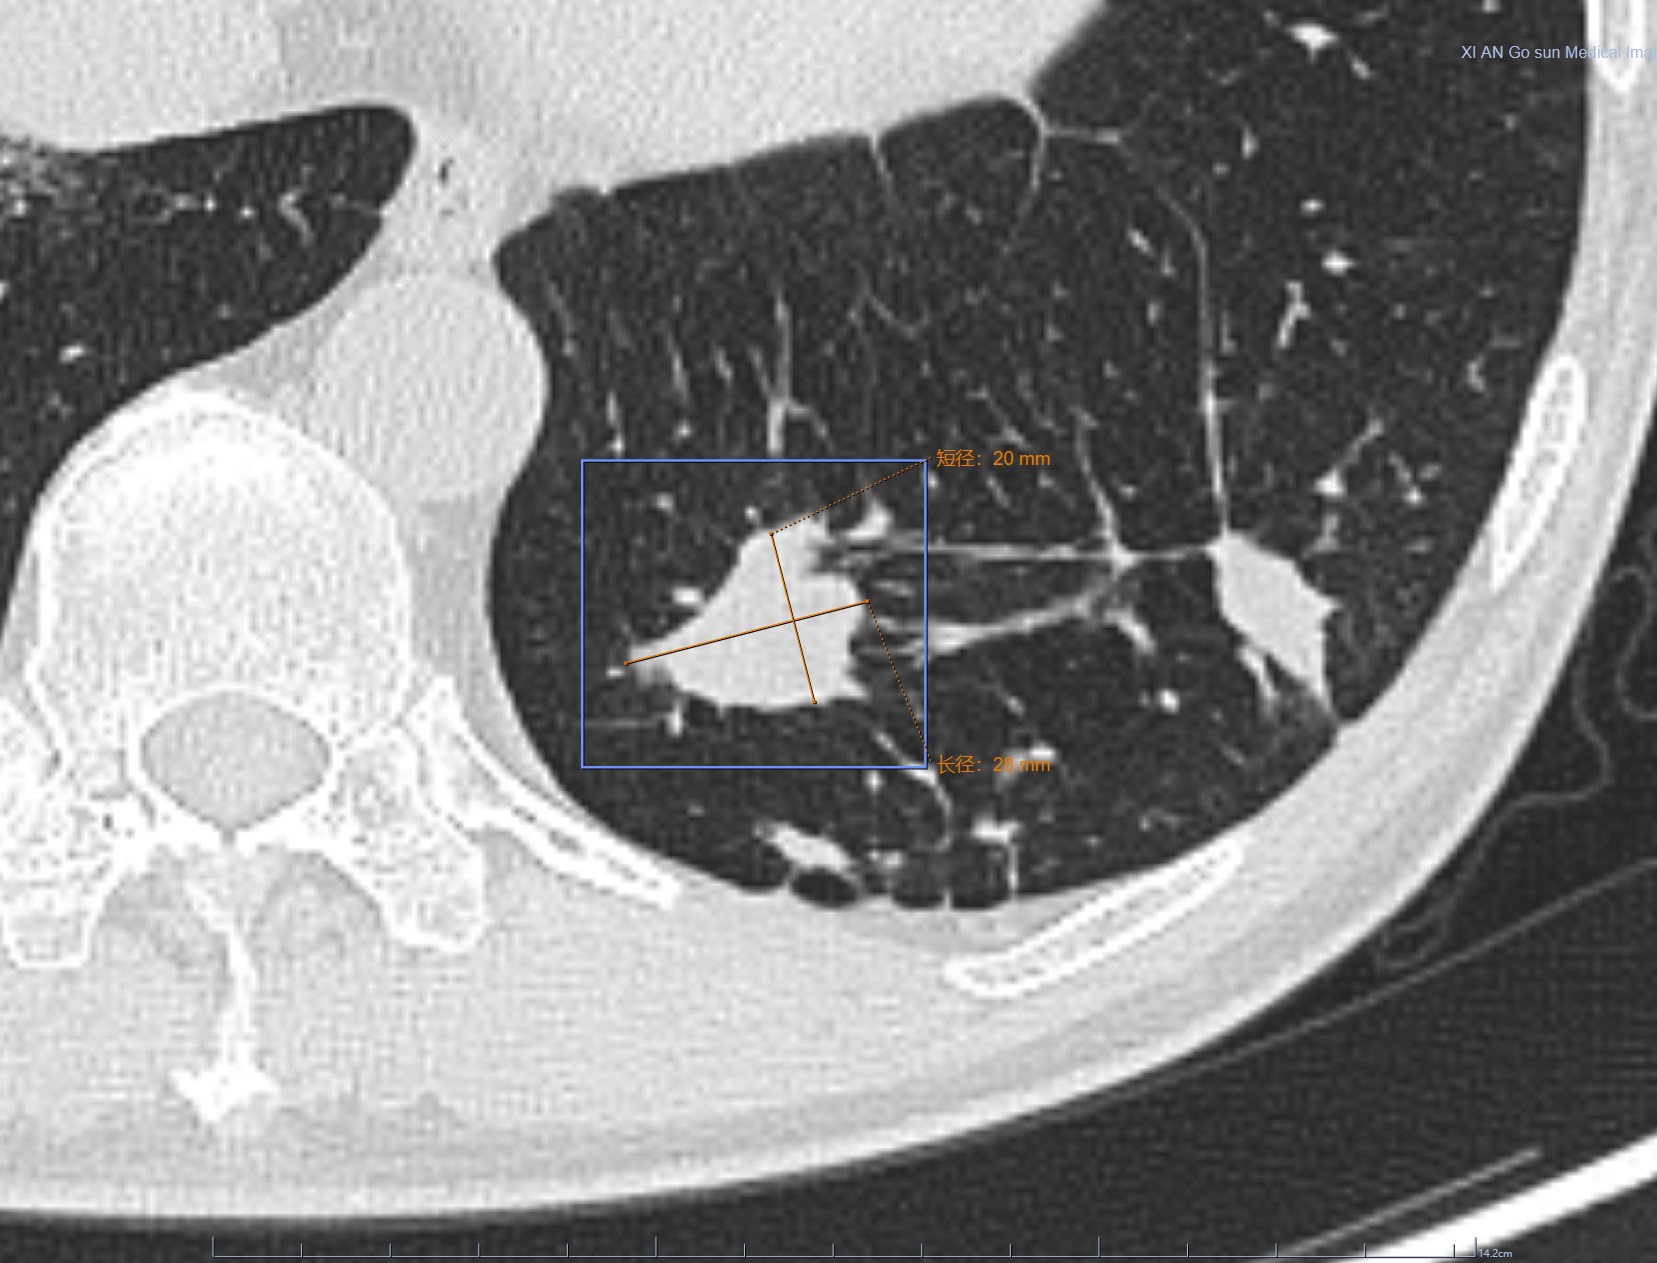

影像学检查特点:右肺上叶尖段实性结节,大小1.2cm×1.1cm×1.0cm,分叶毛刺、胸膜牵拉,最主要的是有两个大的引流血管汇聚,诊断为恶性病变还需要理由吗?不需要理由。这种征象哪个医生也不敢说一定是良性的。建议活检应该是最好的选择。